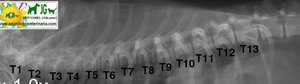

Radiografía laterolateral de la columna torácica canina |